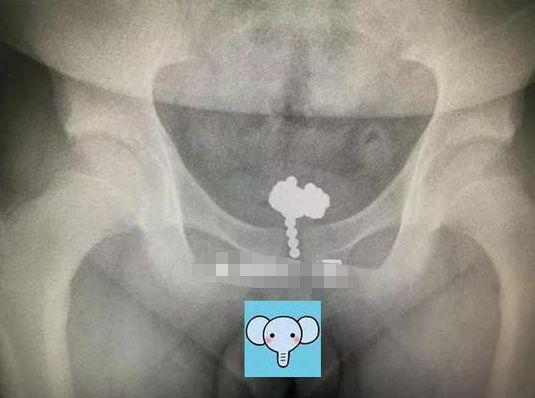

沈医生说,女孩下体是有一个纽扣电池。后遗症还是比较严重的,女孩阴道里面大片烧焦,因为已经 3、4 天过去了,有一些已经变成了一个疤痕。

纽扣电池在体内烂掉了,引发肚子痛,医生连夜做手术将已经发黑的电池取了出来。小姑娘说,电池是自己玩的时候塞进去的。